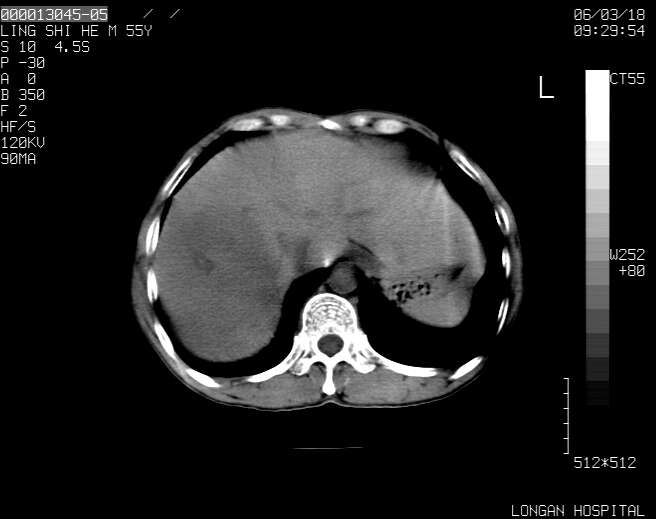

以下是引用guzhongliangddd在2006-3-21 22:13:00的发言:[br]病灶主要位于肝右叶的后份,内见异常血管,门脉主干及右支受侵{提示有癌栓形成},门腔间隙内见增大淋巴结。肝左叶内未见异常。

以下是引用zhuxinli在2006-3-22 1:23:00的发言:[br][br] 病灶主要位于肝右叶的后份,内见异常血管 .门脉右支截断,右叶前段早期强化(考虑动静脉漏),腹膜后肿大淋巴结,病灶逐渐强化,考虑为胆管细胞癌[br]